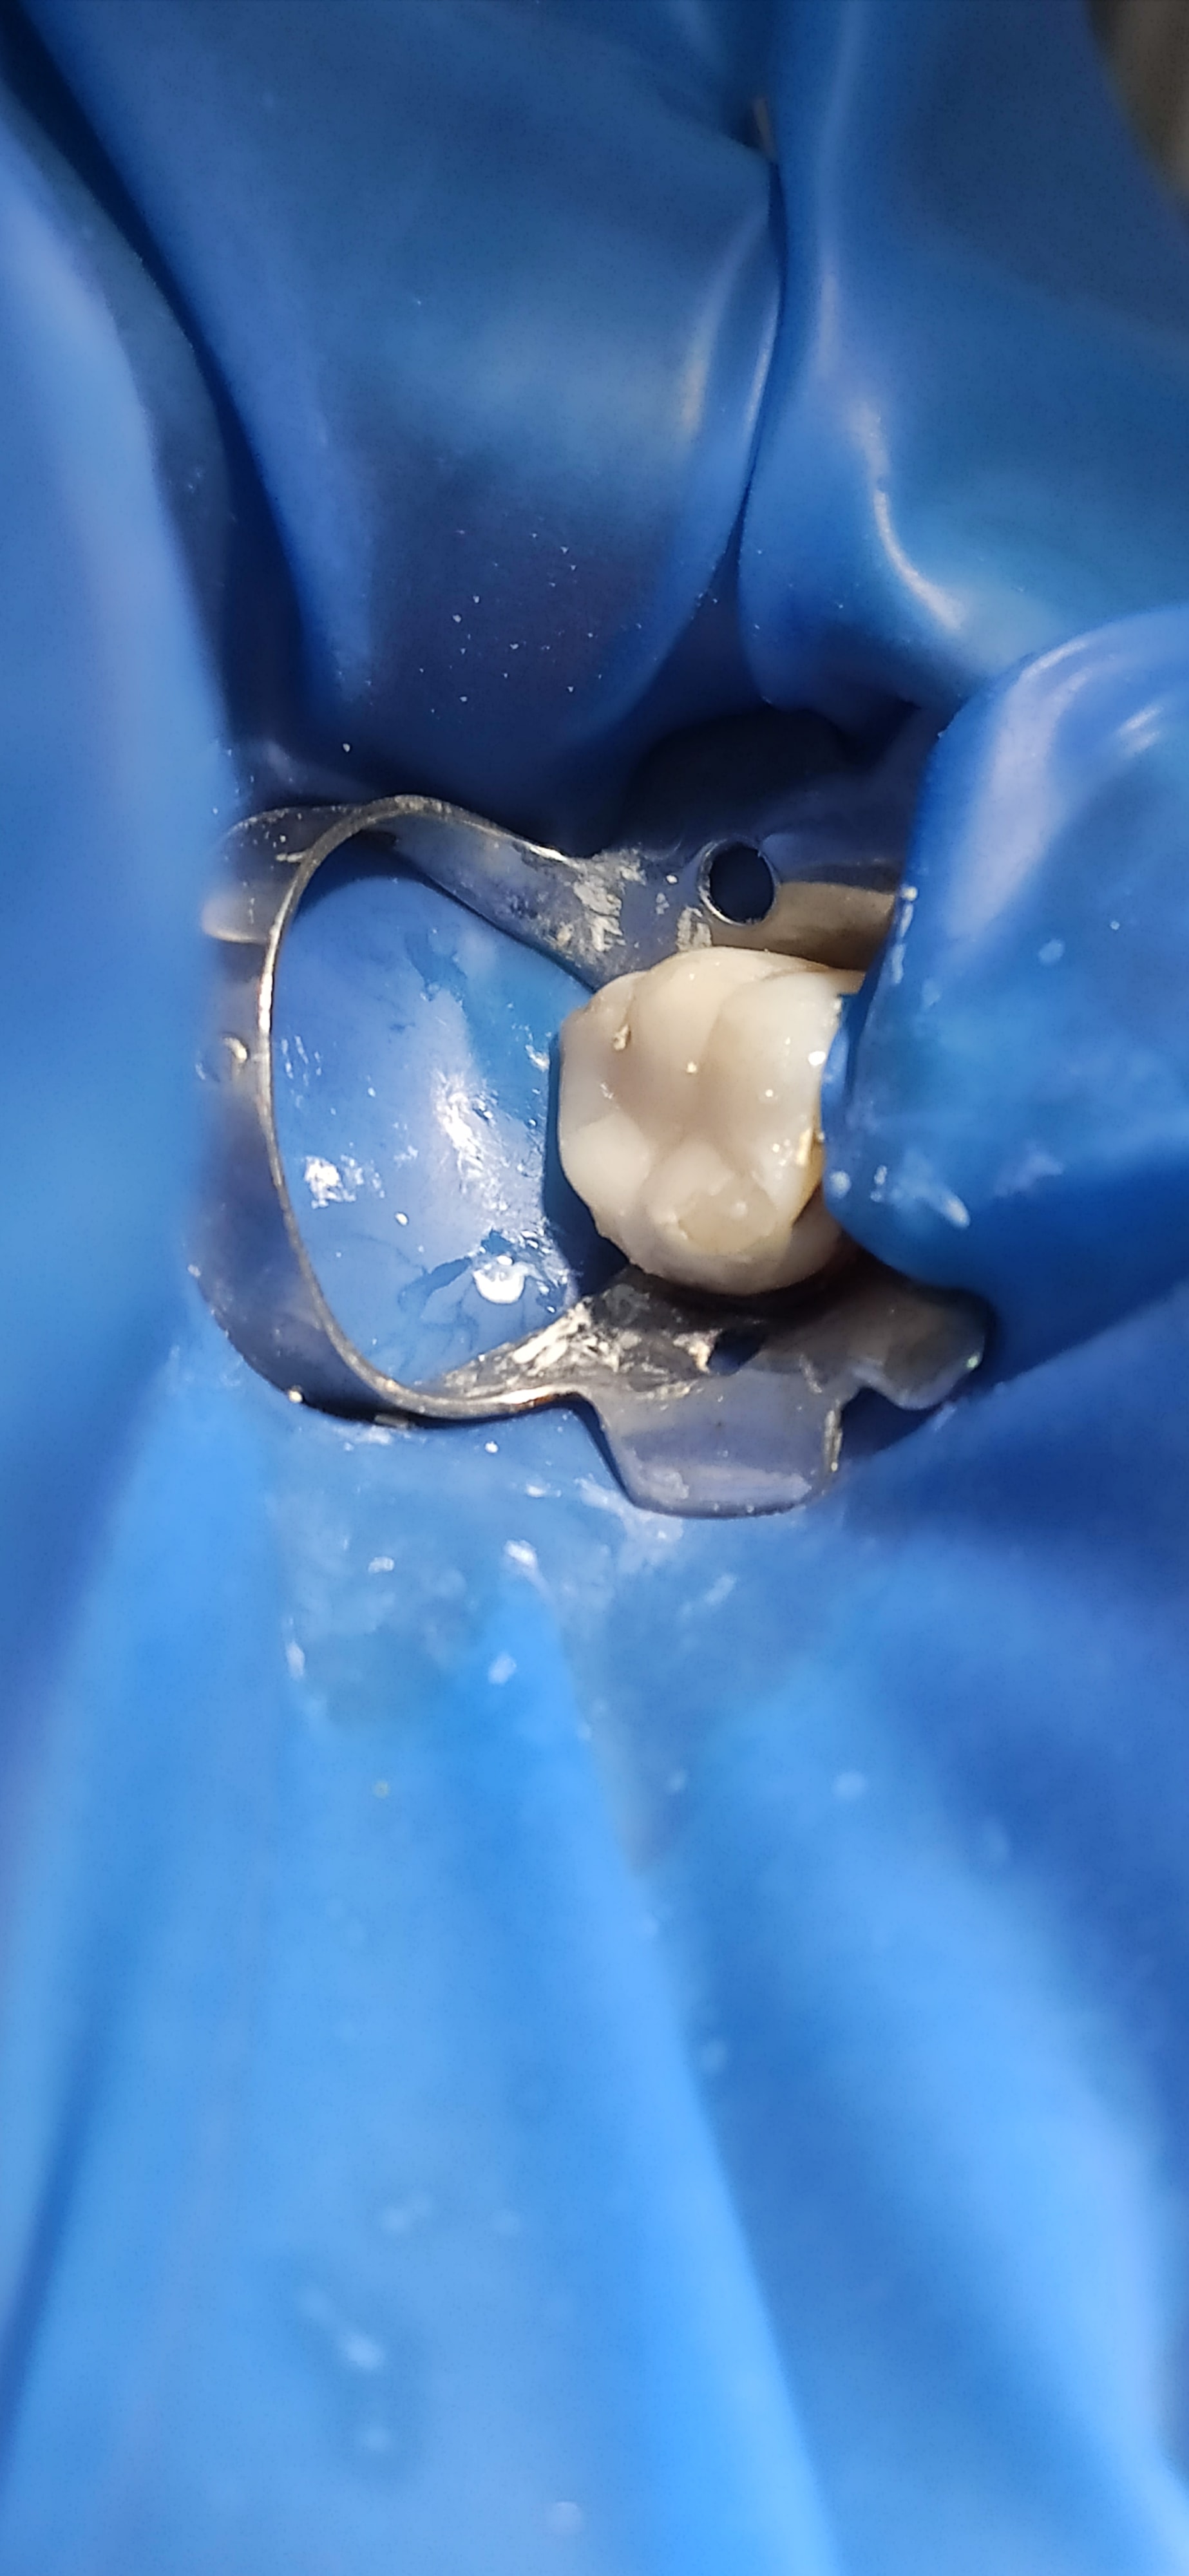

Resultat de mon endo

(2seances d'hydroxyde de calcium, chaque seance irrigation Hypo, toujours sous digue, d'où la décision de laisser la Lime en place, la patiente est informée et rassurée)

Obturation composite direct

pas bravo ;)

superbe anatomie occlusale :)

c est la restauration définitive ?? a mon avis ca va casser assez vite...

Tu as quand même recomposé les 2/3 de la couronne en compo.